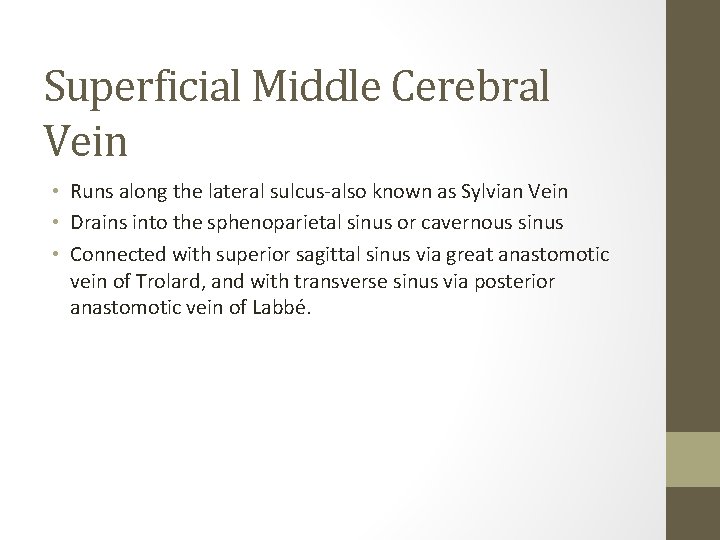

Superficial Middle Cerebral Vein • Runs along the lateral sulcus-also known as Sylvian Vein • Drains into the sphenoparietal sinus or cavernous sinus • Connected with superior sagittal sinus via great anastomotic vein of Trolard, and with transverse sinus via posterior anastomotic vein of Labbé.